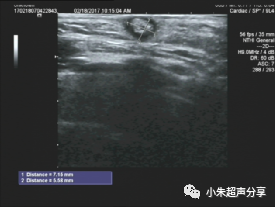

病例3   女 ,12岁,右侧面部毛母质瘤

其内可见斑块状钙化